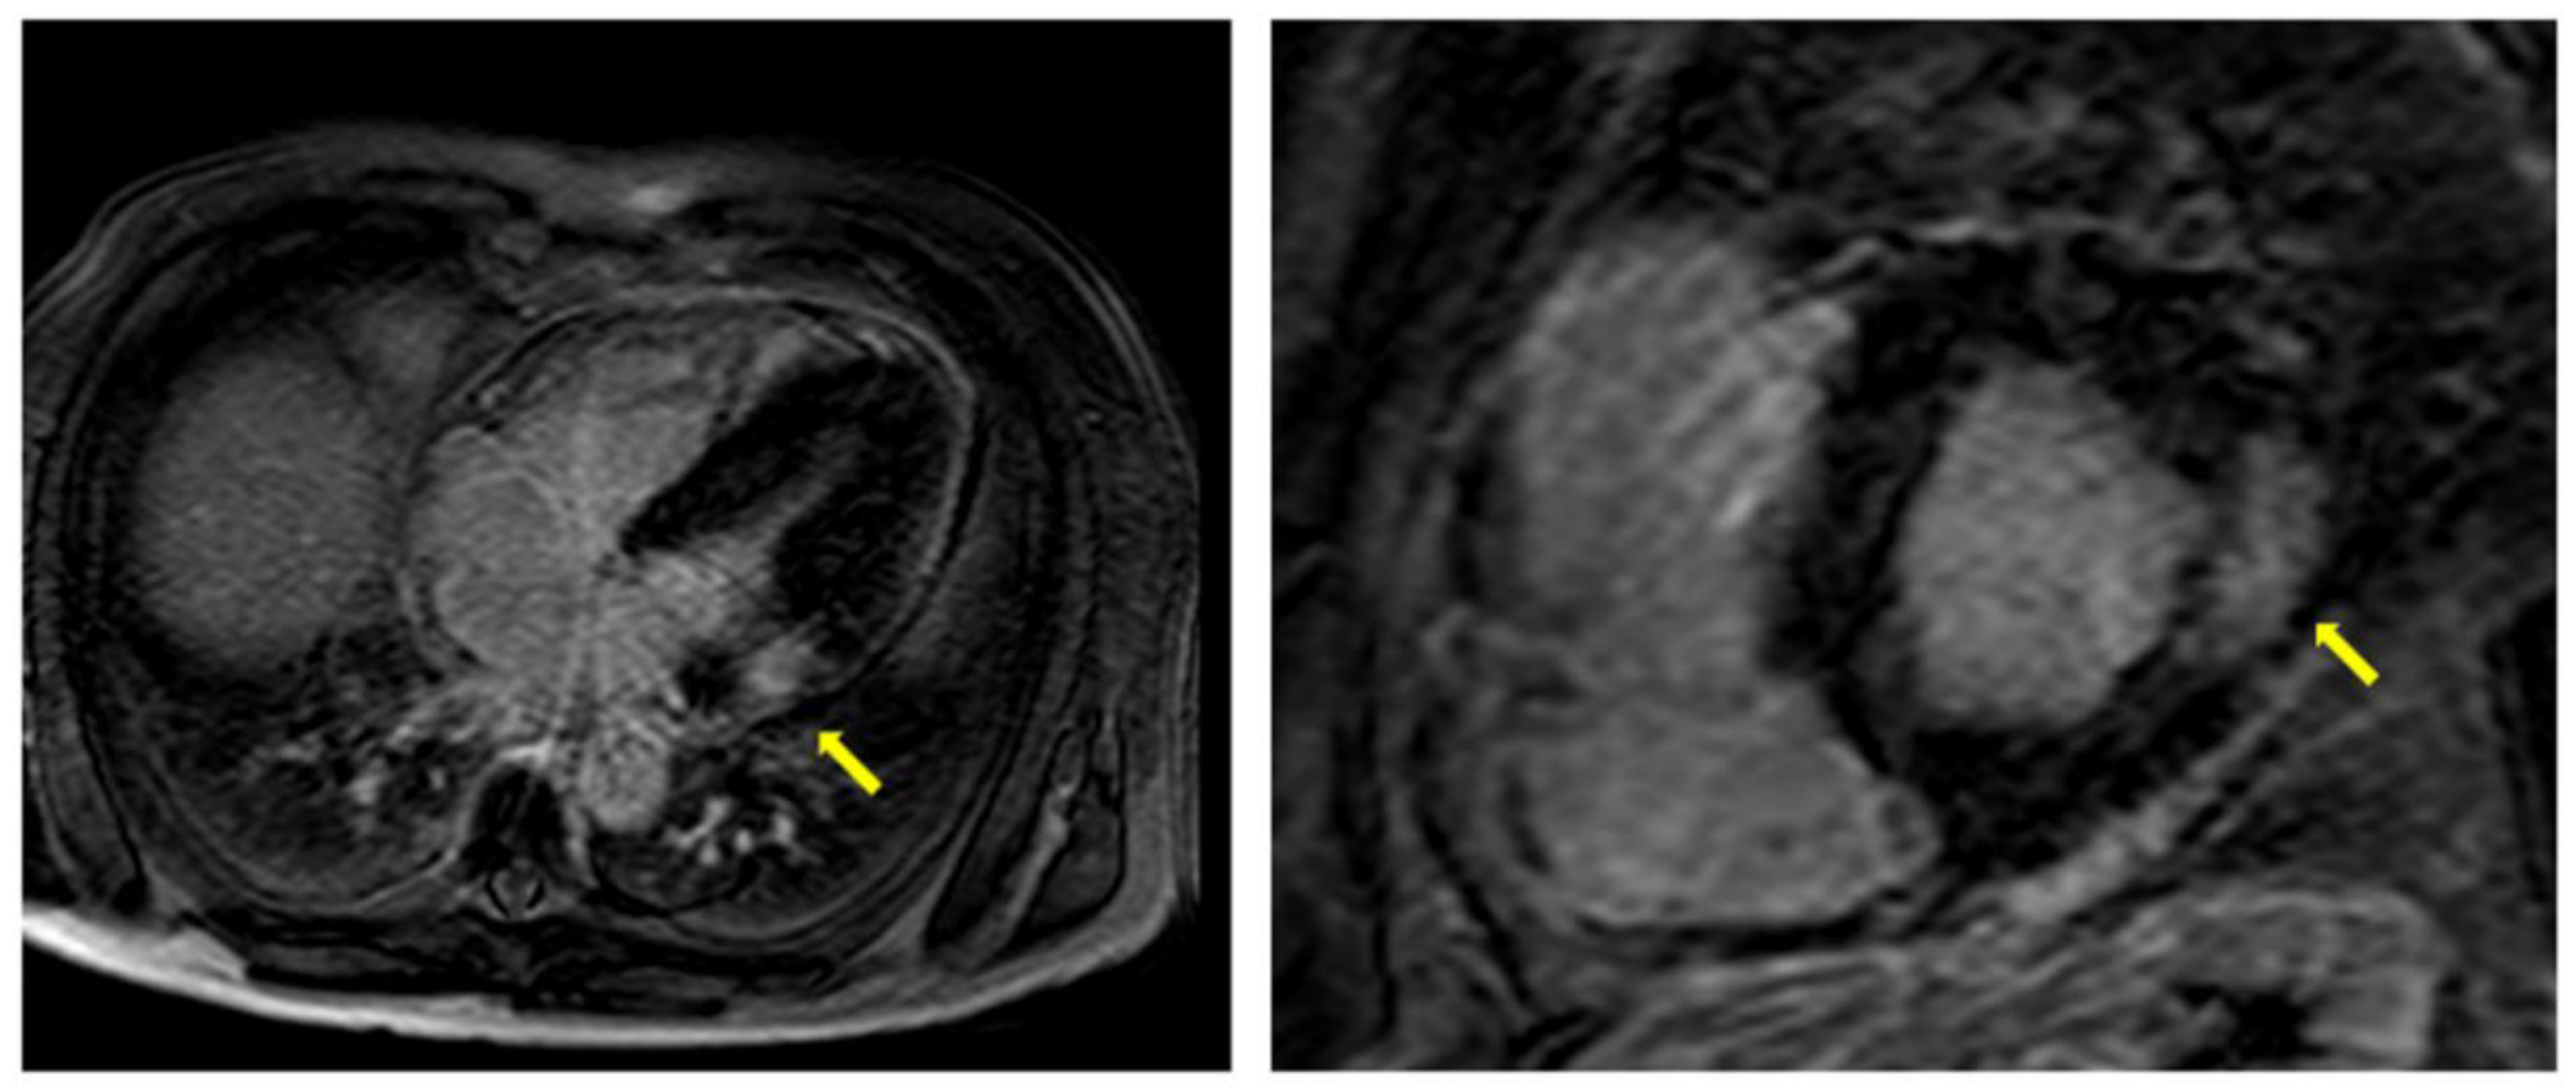

| LGE | -Fibrosis usually localized at mid-wall in the basal infero-lateral area of LV -Very extensive and diffuse in advanced AFD | -Suggestive of AFD when in the typical localization -Additionally present in patients without LVH -Strongly correlated with more CV events |

| T1 mapping | -Lower native T1 times | -Early sign of cardiac involvement -Pathognomonic of AFD -Pseudo-normalization of T1 times correlates with the presence of LGE |

| T2 mapping | -Elevation of T2 times in inferolateral wall or LGE areas | -Suggestive of myocardial inflammation -T2 times elevation correlates with troponin elevation -No pathognomonic |